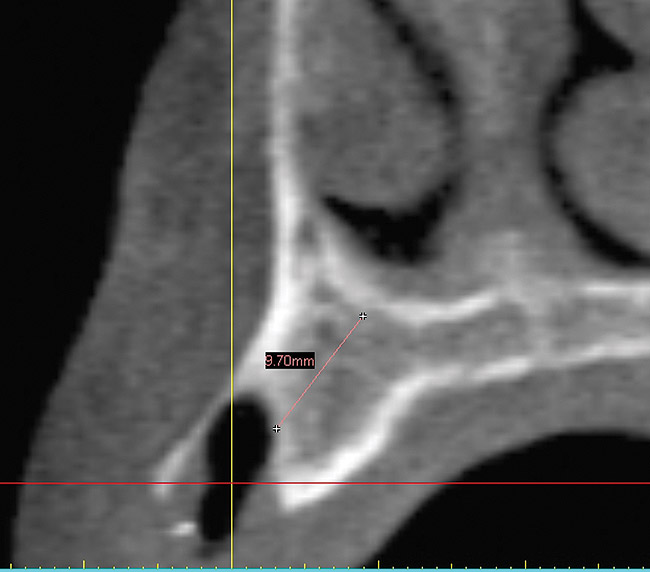

Figure 3  Cross-sectional view showing large defect with 9 mm of remaining bone.

Figure 3

A 56-year-old woman in good health presented with recent extractions and a fully edentulous maxillary arch and edentulous posterior mandibular areas. A CBCT scan 3D view revealed large osseous defects in the maxillary arch that required grafting before implant placement (Figure 1). The treatment plan was made for maxillary ridge augmentation followed by fixed prosthesis-supported dental implants in all of the edentulous areas. The mandible did not require grafting. The patient was wearing a full upper denture during the entire grafting and subsequent implant healing time period. The maxillary arch showed large defects on the axial view of the CBCT (Figure 2). A cross-sectional CBCT view also showed deficient height of bone with a vertical height of 9.7 mm (Figure 3). Upon full-thickness reflection, large deficient areas of the ridge were seen that required grafting before implant placement (Figure 4).

A DFDBA bone-graft putty (Regeneform) was used to graft the entire maxillary arch. All extraction defects were degranulated, the bone was decorticated to allow bleeding, then the DFDBA putty was placed and covered with resorbable collagen membranes (Biomend Extend, Zimmer Dental) (Figure 5). Primary closure was obtained and the patient wore her denture after a soft reline for a period of 6 months (Figure 6). At 6 months post-graft, a CBCT scan revealed substantial graft material from both an axial (Figure 7) and a crosssectional view, showing more than 15 mm of bone height (Figure 8). The 3D view from the CBCT also showed substantial ridge changes in both height and width (Figure 9). Using a CBCT software program (SimPlant, Materialise Dental Inc, Glen Burnie, MD), implants were planned for placement (Figure 10). As per the CBCT plan, 11 internal hex implants (BioHorizons, Birmingham, AL) were placed in the grafted bone (Figure 11). The ideal bone height allowed implant placement in an ideal position with relation to esthetics and occlusion.